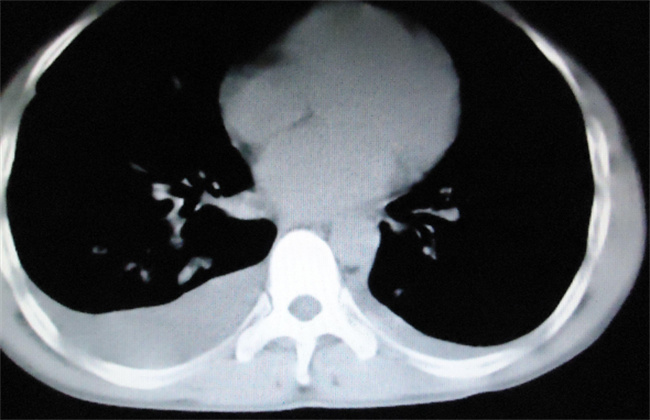

有些良性确诊患者在平台上马上就会晒出自己的CT报告,并且还会显示肺部会有明显的白肺情况,建议大家在新冠感染康复之后,就应该马上去做肺部CT检查。许多的人在转阴之后还有咳嗽,而且咳嗽持续了较长的一段时间,因此都会选择来到医院做肺部CT检查,最近一段时间做肺部CT检查的人非常的多,甚至已经达到一个人满为患的现象,但是其中出现严重肺部疾病的人并不是很多,估计仅仅只有1%~2%左右。

如今所出现的这些肺部影像并非是医学上所说的白肺。临床上主要是指一种肺源性的肺水肿,而且在显示上面就会看到有白色的斑影片,一般这就是因为病毒感染所导致,一般情况是比较轻微的,并不需要过于的担心,再过了一段时间之后就会逐渐的恢复。除了新冠病毒之外结合杆菌感染又或者是流感病毒都有可能会导致肺炎的出现,一般的情况下都是可以恢复的,哪怕是一些比较严重的患者在干预之下也会慢慢的好转,因此也并不需要特别的惊慌。实在担心的话,就可以直接选择去拍一个胸片,就可以显示出很多的问题,然后就可以采取针对性的治疗。